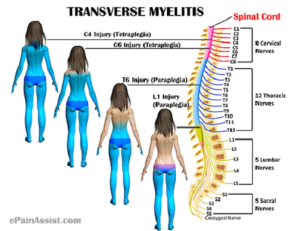

میلیت عرضی یک اختلال است که به دلیل التهاب طناب نخاعی ایجاد شده و هر دوسمت سگمان نخاعی درگیر شده را دربرمی گیرد.

یک بخش حسی باند مانند از تنه عبور می کند که در پایین این بخش تغییرات حسی ایجاد میشود.

در واقع واژه عرضی نشان می دهد که در سطح مشخصی از طناب نخاعی این اختلال معمولا ایجاد می شود.

میلیت عرضی جزئی یا میلیت جزئی عنوانی است برای توصیف این بیماری زمانی که بخشی از عرض طناب نخاعی دچار التهاب شده است.

این اختلال افراد را در هر سن ،جنس و نژادی می تواند درگیر کند و پیک سنی آن شامل دو بازه ۱۹-۱۰ سال و ۳۹-۳۰ سال است.

- ضعف در پاها و دست ها